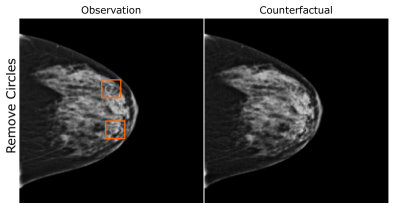

EMBED

Using prior insights, we apply our mechanisms to a real-world artefact removal task on the EMory BrEast imaging Dataset (EMBED) (Jeong et al., 2022). Schueppert et al. (2024) observe that triangular and circular skin markers are spuriously associated with breast cancer in classifiers due to shortcut learning (Geirhos et al., 2020), and manually labelled 22,012 affected mammograms. Using this dataset, we train a significantly scaled-up, amortised, anti-causally guided semantic mechanism () to remove skin markers. We model triangular markers (), circular markers (), breast density (), and cancer () as independent parents of the mammogram , and remove artefacts by intervening on and while holding and fixed. Figure 6 shows that our mechanisms effectively remove artefacts and can disentangle representations for triangles and circles. We successfully remove of triangles and of circles in our test set - a noteworthy result given the dataset’s small size and the scarcity of labelled skin markers (Appendix I).